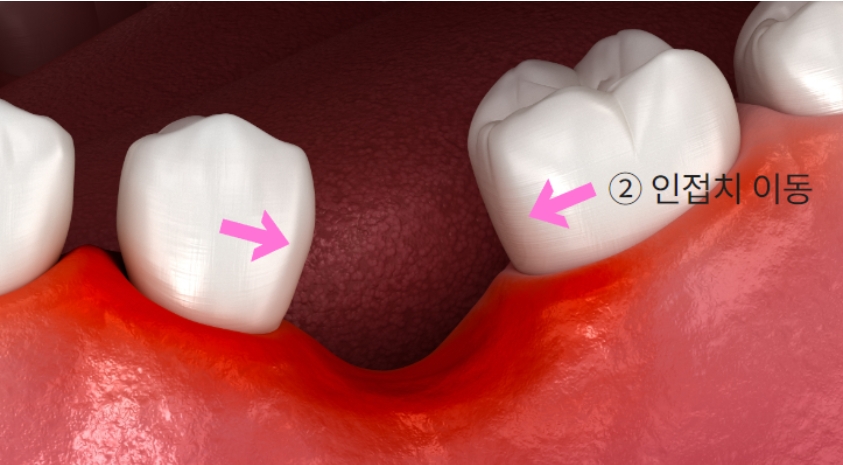

2. 인접치 이동

치아는 빈 공간으로 이동하려는 성질이 있기 때문에, 만약 이빨이 하나 빠지면

옆에 있는 인접 치아들이 그 빈 공간 쪽으로 이동하거나 기울어지게 됩니다.

인접치 이동 현상

그렇게 되면 치아 사이사이가 벌어져서 미관상 좋지 않고,

발음이 새거나, 벌어진 사이로 음식물이 잘 끼어서 치주염을 유발하는 등

여러 가지 문제를 일으킬 수 있습니다.

또한 만약 치아 이동이 많이 발생했다면, 나중에 임플란트를 할 자리가 없어지기 때문에

교정을 통해 치아를 다시 원래 자리로 돌려놓은 다음에 임플란트를 심어야 하는 상황이 생길 수 있습니다.

그럼 비용도 배로 들겠죠.